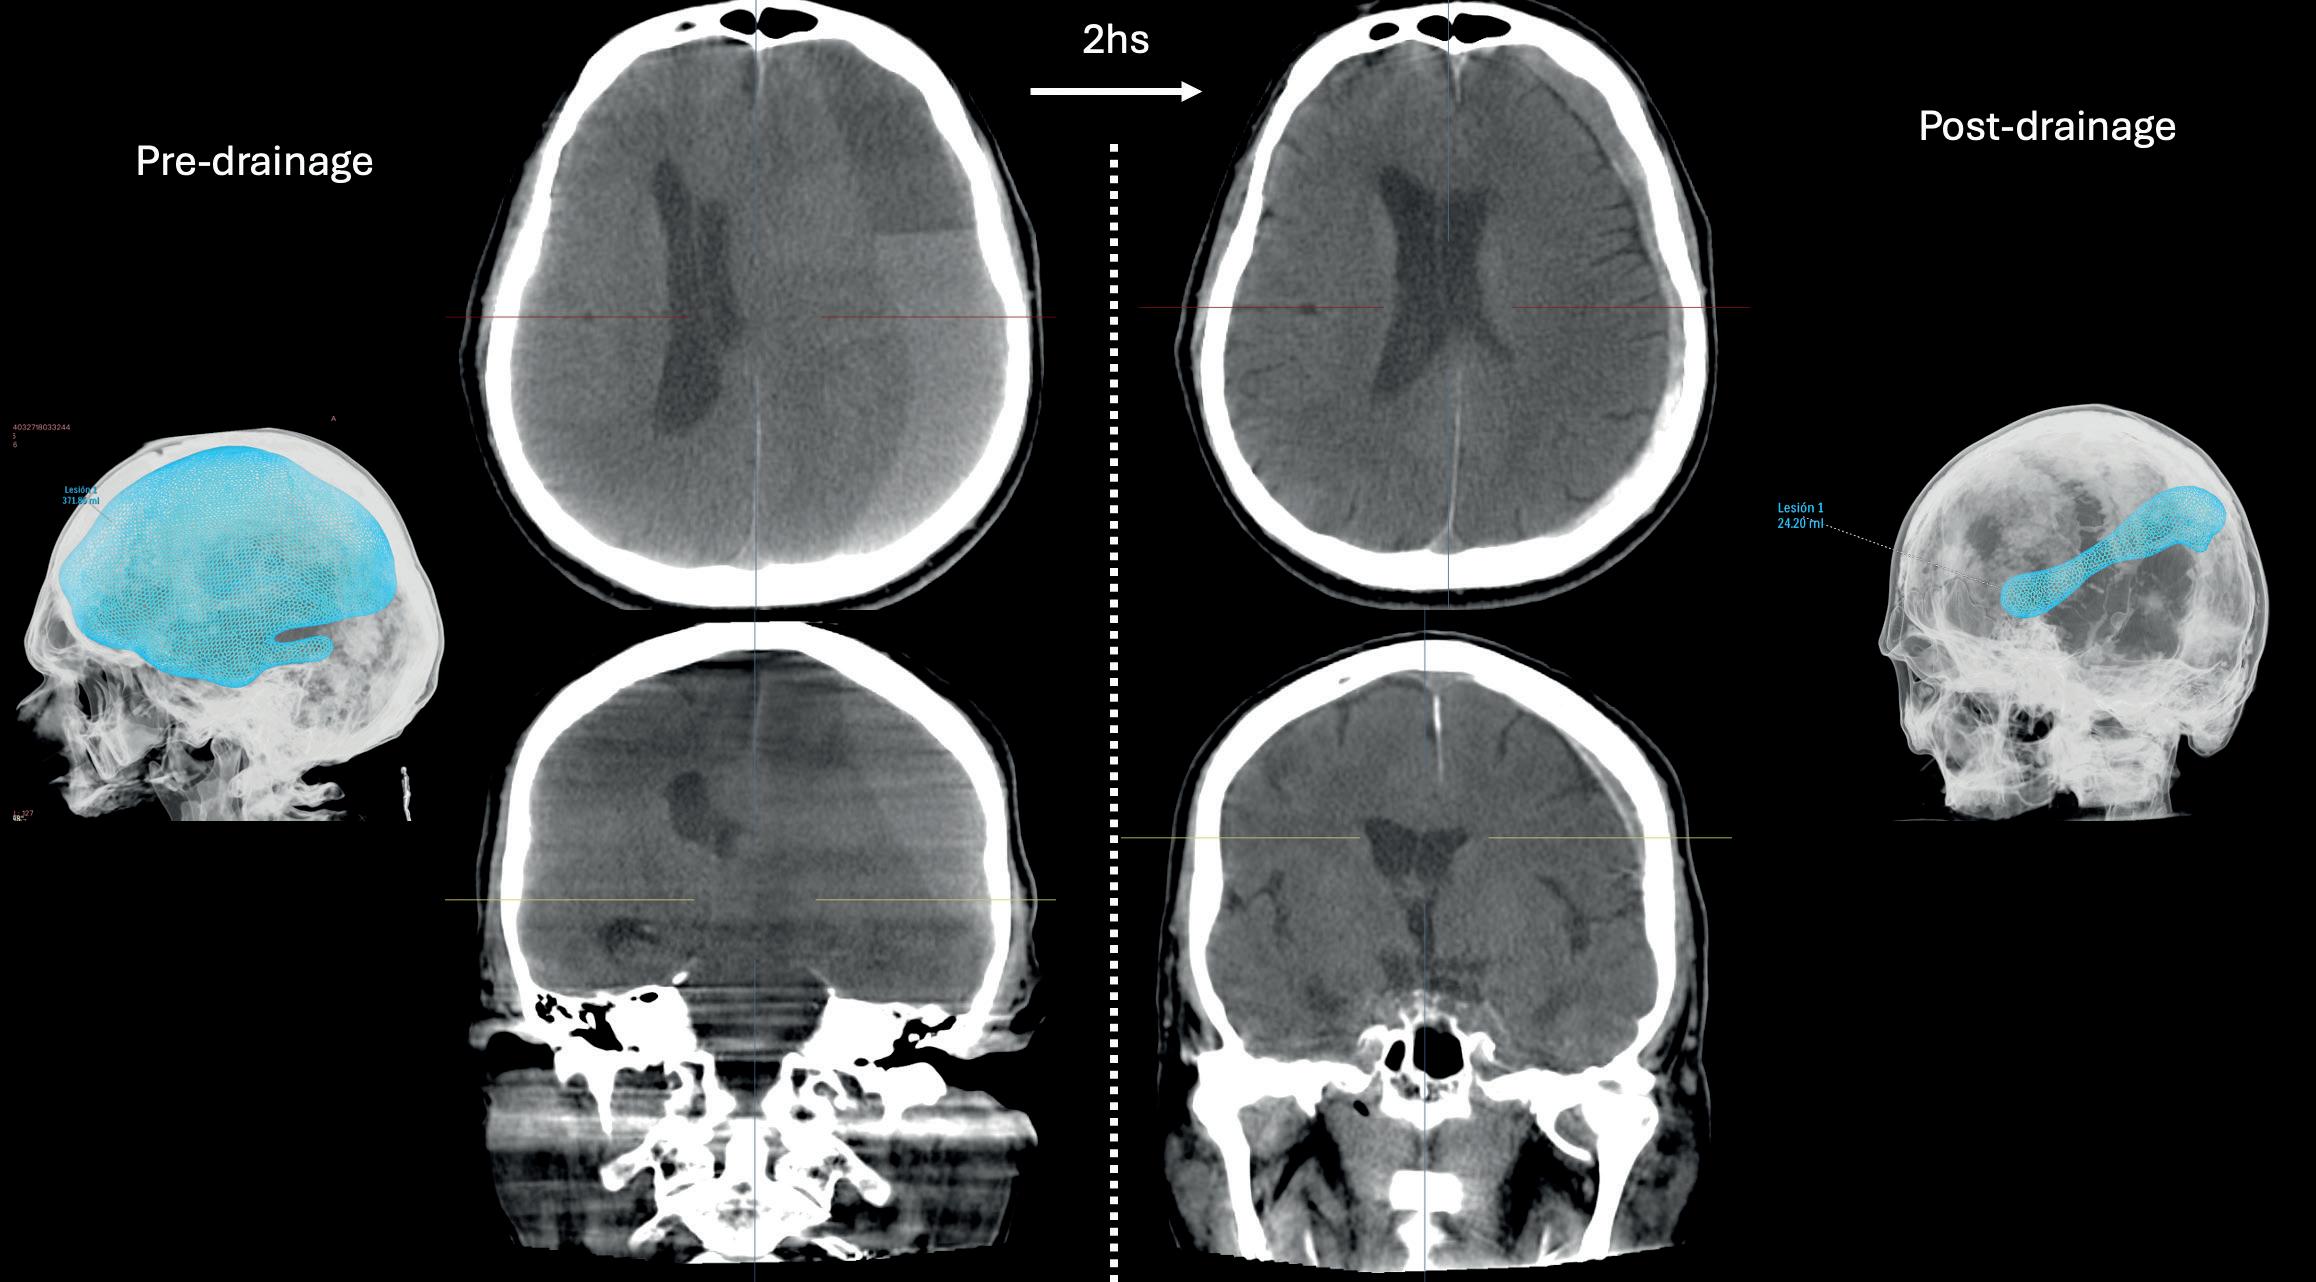

n STUDY HIGHLIGHTS RESOURCE-EFFICIENT SUBDURAL HAEMATOMA TREATMENT: Performing a middle meningeal artery (MMA) embolisation procedure during the same anaesthesia session as a burr hole evacuation surgery represents a safe and potentially resource-efficient approach to the management of chronic subdural haematoma (cSDH), as per a retrospective review published by Charles Matouk (New Haven, USA) and colleagues. in the Journal of NeuroInterventional Surgery

Performing a middle meningeal artery (MMA) embolisation procedure during the same anaesthesia session as a burr hole evacuation surgery represents a safe and potentially resourceefficient approach within the management of chronic subdural haematoma (cSDH).

THIS IS THE KEY FINDING OF A retrospective review published recently in the Journal of NeuroInterventional Surgery (JNIS) by Charles Matouk (Yale School of Medicine, New Haven, USA) and colleagues.

“The development and evaluation of new approaches with the potential to improve the safety and efficiency of MMA embolisation in cSDH management is essential,” Matouk told NeuroNews. “The field is still in its infancy, and we have a lot of work to do to understand who will benefit most and how to streamline the patient experience.”

In order to evaluate preliminary

experiences with this combined approach, Matouk and colleagues performed a retrospective review of all patients who underwent MMA embolisation and burr hole surgery during the same admission at a major academic institution in the US state of Connecticut between 2019 and 2024. Patients were dichotomised by those undergoing both procedures during a single anaesthesia session

(combined) or across two separate sessions (separate). The authors relay in JNIS that baseline demographics, comorbidities and complications were compared, with primary outcomes of the study being in-hospital and 90-day rates of complications and reoperations.

A total of 103 patients (median age, 74 years) were included in the study, with 33.9% of these patients being part of the combined cohort.

Demographics, comorbidities and radiographic characteristics were ultimately found to be similar between the two study cohorts.

Matouk and colleagues relay that, while cumulative procedure times were similar between the combined (96 [82–127] minutes) and separate (85 [71–110]

minutes) groups, the total anaesthesia time was “significantly longer” for patients undergoing separate versus combined procedures (225 [193–264] vs 165 [145–183] minutes, respectively; p<0.001).

The researchers found that there were no differences in the rates of in-hospital access site complications, reoperation, stroke or mortality between the cohorts—and, while the combined study cohort trended towards having a shorter length of stay compared to the separate procedure group (5 [4–7] vs 6 [5–8] days, respectively; p=0.058), there were no differences in complication or reoperation rates within 90 days either.